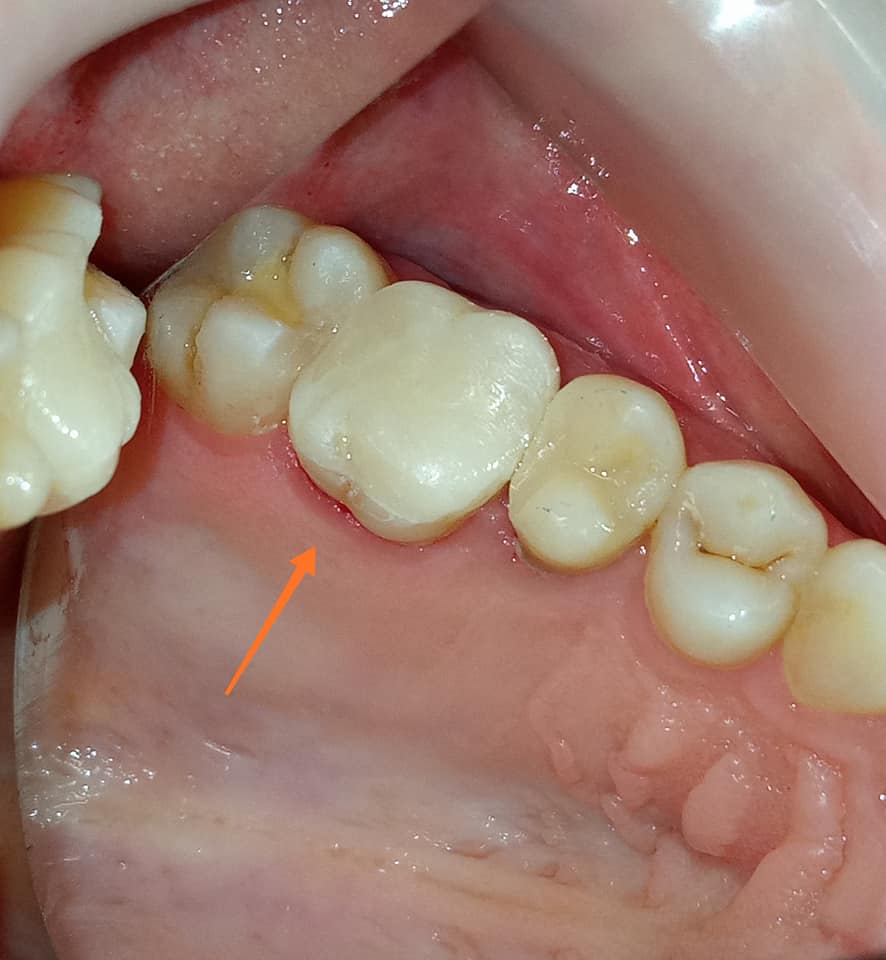

Τελική κλινική εικόνα του ολοκεραμικού ένθετου στον προγόμφιο